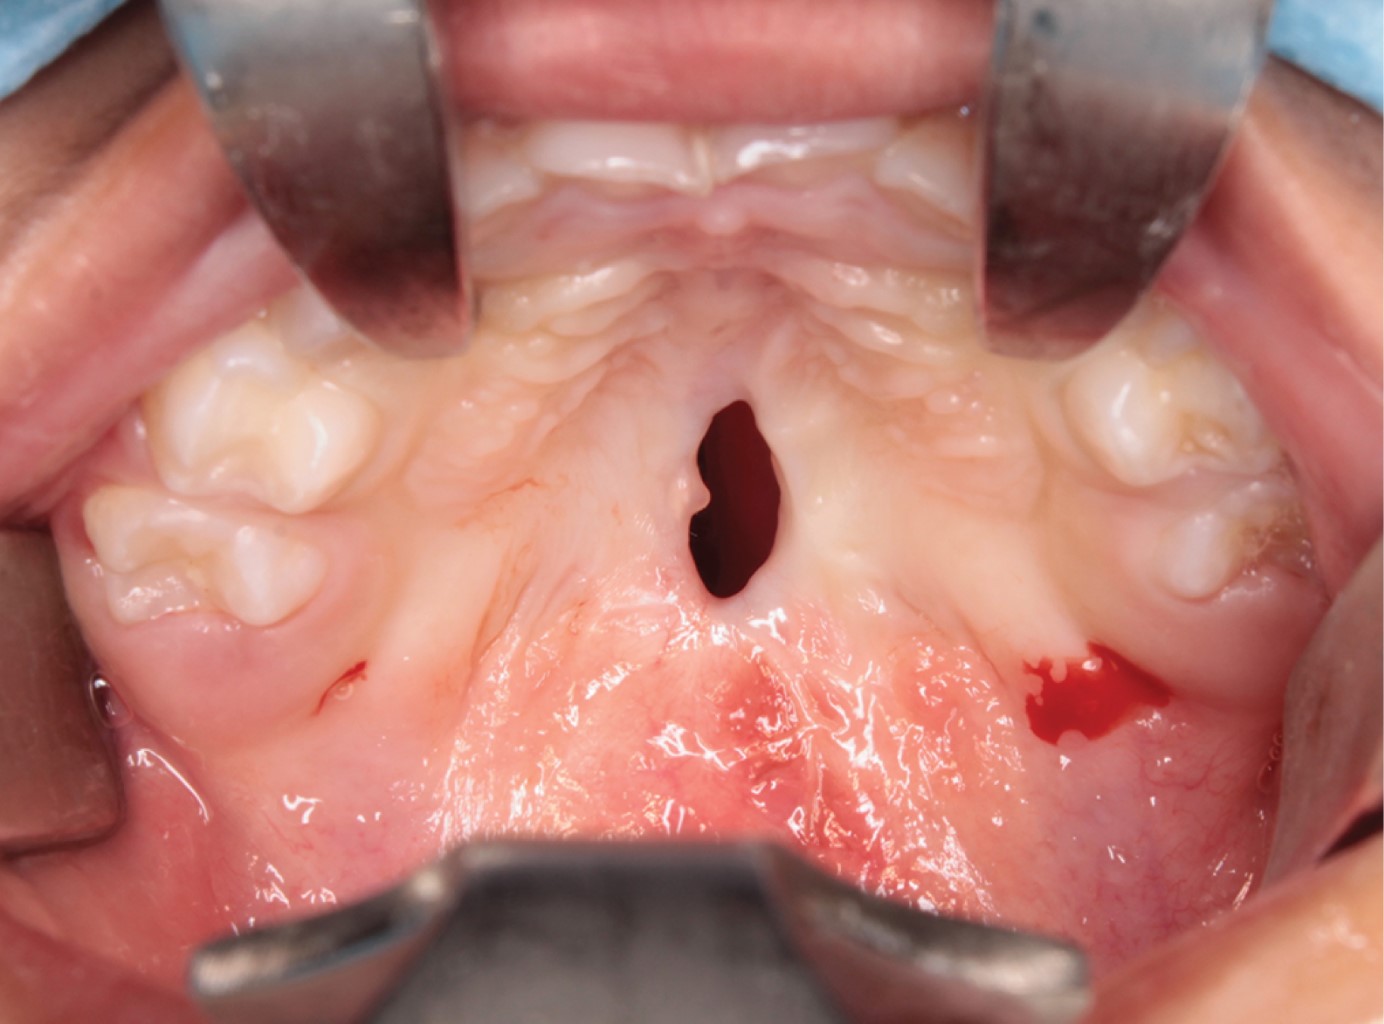

Se presenta el caso de un paciente pediátrico masculino, quien fue llevado al Servicio de Cirugía Maxilofacial del Centro de alta Especialidad "Dr. Rafael Lucio" a la edad de un año cinco meses. Fue valorado y diagnosticado con fisura de paladar secundario clasificación II de Veau (Figura 1), por lo que se le realizó palatoplastia mediante técnica de veloplastia intravelar bajo anestesia general balanceada; la cirugía se llevó a cabo sin complicaciones ni eventualidades (Figura 2). El paciente fue dado de alta; acudió a controles posquirúrgicos a la semana, al mes y a los seis meses; durante este seguimiento fue posible observar la presencia de una fístula palatina Pittsburgh IV +, Cohen II, la cual provocaba paso de líquidos desde la cavidad oral a la nasal (Figura 3).

Figura 4